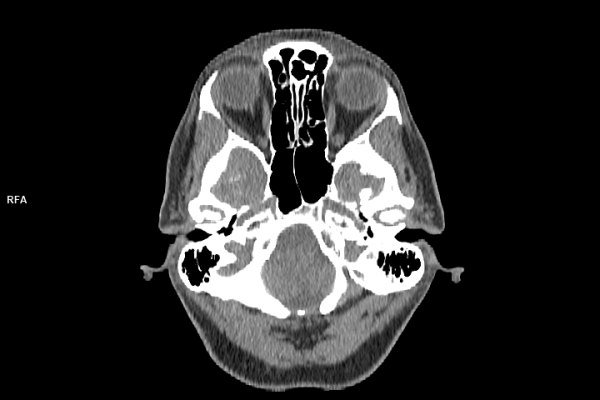

CT Untersuchung Bild

• Neuroradiologie

Was ist der Unterschied zwischen einer MRT- und einer CT-Untersuchung?

Die MRT (Magnetresonanztomographie) arbeitet mit Magnetfeldern und Radiowellen und eignet sich besonders für Untersuchungen der Weichteile wie Gehirn, Muskeln oder Gelenke. Die CT (Computertomographie) nutzt Röntgenstrahlen und liefert schnelle, hochauflösende Bilder, insbesondere für Knochen, Lunge oder innere Organe. Die Wahl der jeweiligen Untersuchung richtet sich an das individuelle Krankheitsbild und wird bei der Überweisung festgelegt.